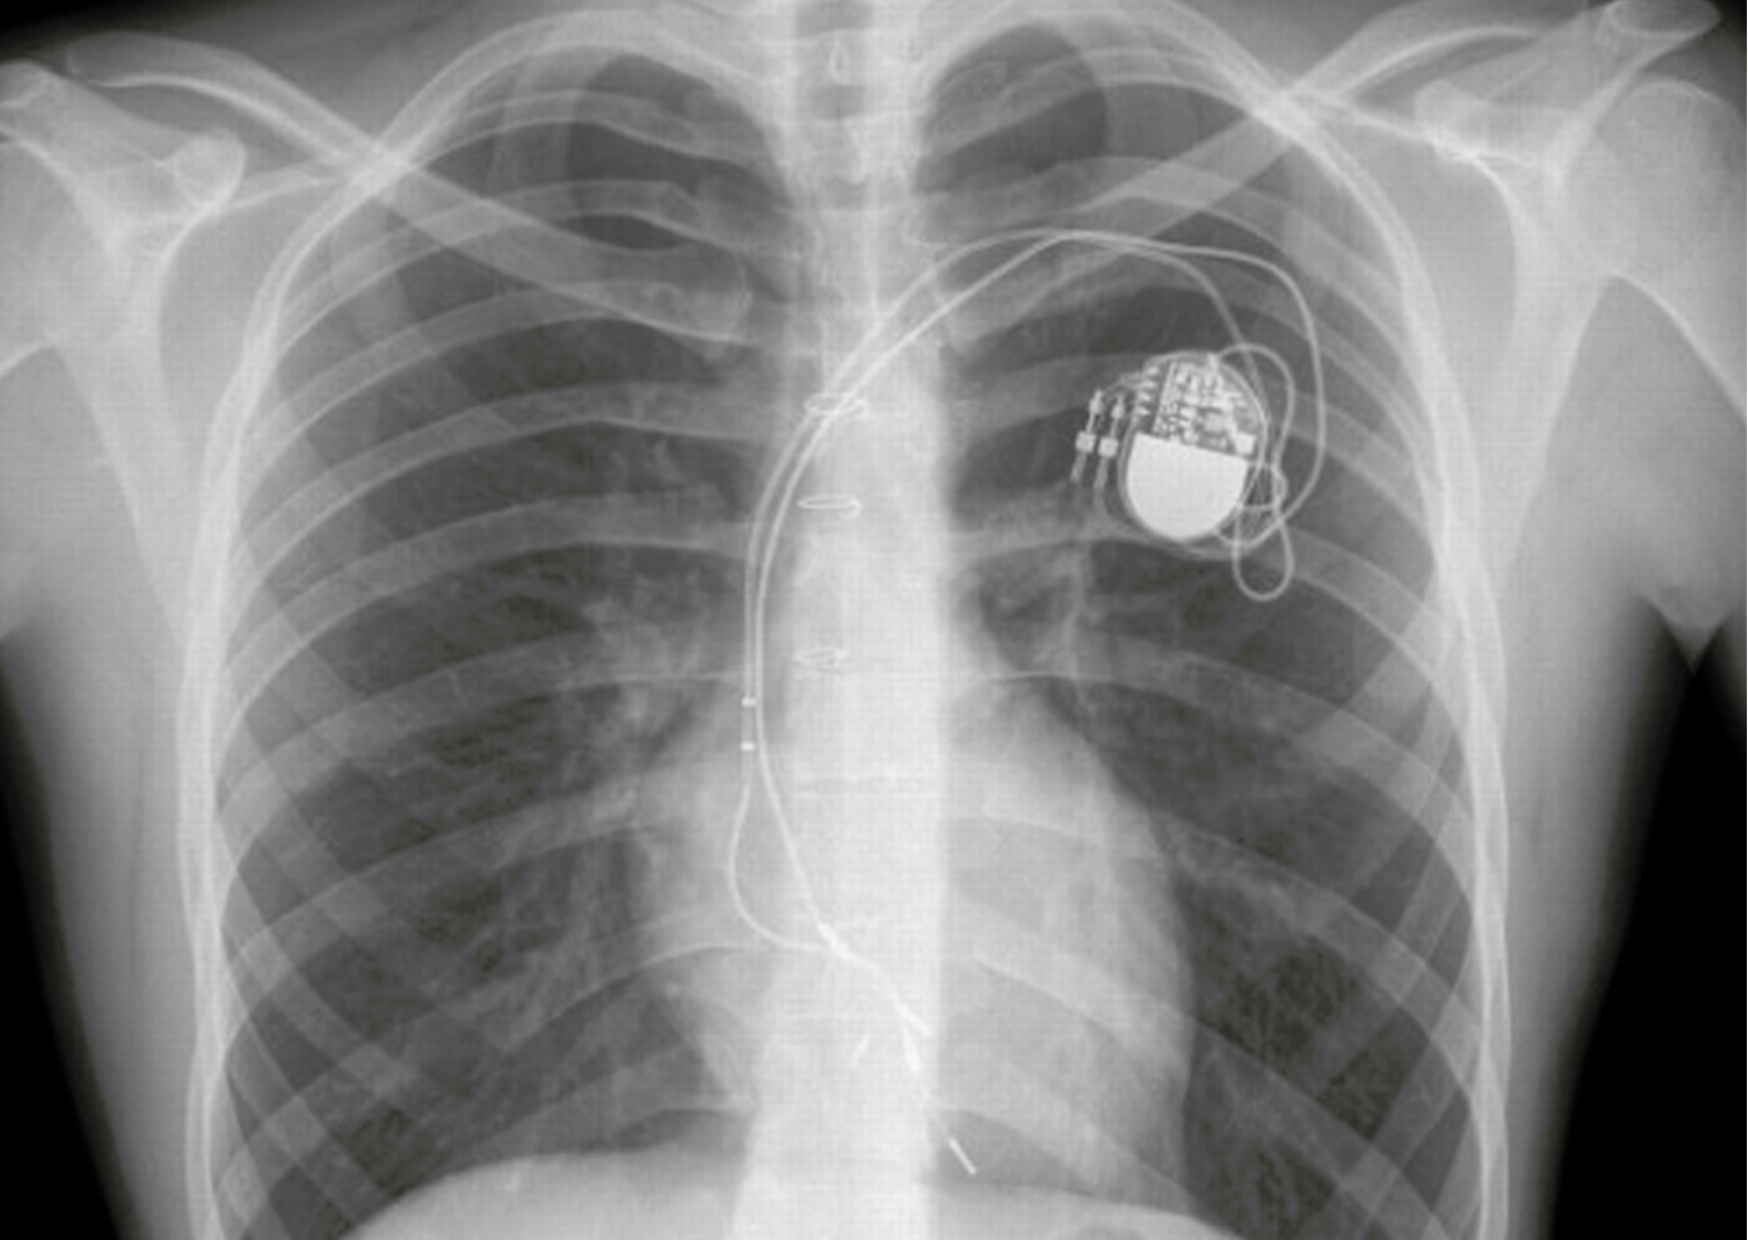

Как следствие, после таких сложных операций на открытом сердце, часто бывают различные аритмии. К сожалению, эта отвратительная хрень не обошла меня стороной. Сердце по строению вроде бы было уже здорово, но ужасная брадикардия не давала вздохнуть с облегчением (смотрите-ка, эта фраза заиграла новыми красками в данном контексте). Врачи из НИИ, в котором я наблюдалась, задумались над установкой кардиостимулятора, но решили - чем позже, тем лучше. Так я ходила на свободе с 4 до 13 лет, с ритмом 35-40 уд./мин. Прямо как остывающая ведьма. Или легушька. Но однажды на плановом осмотре на меня напялили холтер и отправили сдавать кровь. Ну а я ж кисейная барышня и это дело ой как не люблю. Грохнулась в обморок прямо на пробирки с кровью. Тут без комментариев - зрелище было то ещё. Но самое классное зрелище записал висящий на мне холтер — аж 12-секундную остановку сердца. После чего моя лечащая врач сильно как-то изменилась в лице и затребовала срочной имплантации кардиостимулятора. Так, в возрасте 13 лет, мне вшили в плечо мой первый двухкамерный Sigma. Он был настоящим героем и проработал 11 лет. Затем на контрольном осмотре оказалось, что заряда батареи практически не осталось, да ещё и сломался желудочковый электрод. Так мне поставили моего второго героя — Vitatron, вы можете наблюдать этого красавчика на фото.